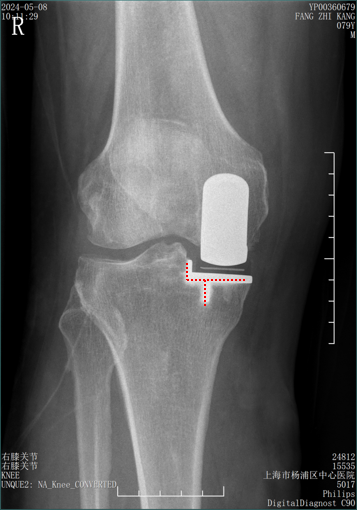

标准正侧位片拍摄方法(门诊)

-

在前后位投照中,透视监控下调整X线束和下肢位置,直到胫骨假体完全前后端一致(end on)后拍X光片。

光束与正交平面对准( 水平底板与垂直侧壁和龙骨 ),从而提供准确性和重现性高的X光片。

在侧位投照中,膝关节屈曲20-30°,X射线束以股骨假体为中心,平行于地板。

胫骨假体不能提供任何垂直表面 ,水平面又被侧壁遮挡,所以侧位不如前后位精确性和重复性高。

在前后位片(AP),bearing在胫骨底板内外位置通过不透射线“—“和“. ”的标记推断出来。

Bearing的外侧面距离胫骨假体侧壁2-3mm(屈曲位时为1mm,伸直位胫骨发生了外旋)。

Bearing 中立位( X-ray正位)

Bearing 内旋( X-ray正位)

Bearing 外旋( X-ray正位)